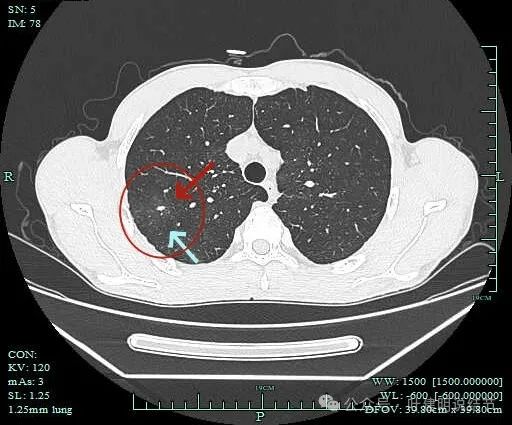

右上病灶1:

病灶出现,密度较高,不是圆形或类圆形,边缘略模糊。

病灶似乎有卫星灶,中间有小空泡征,边缘有晕。

感觉周围略糊,有晕的感觉。

上面层面密度较高。

似乎有毛刺征,但膨胀性不明显。

有部分边缘显毛糙。

点状高密度,有晕的感觉。

点状高密度结节。

点状高密度之外,蓝色箭头示周围有淡磨玻璃影。

风轻云淡磨成分明显且轮廓不清。中间的点状高密度显得不够致密,缺乏收缩力。

边缘区仍有淡磨形态的晕

此灶从连续层面上看,是自右上前侧斜行向左下后侧延伸的,整体病灶偏长条些,而且有晕、有淡磨成分,实性部分缺乏收缩力或膨胀性,更符合炎性病灶的恢复期或吸收不全的阶段。